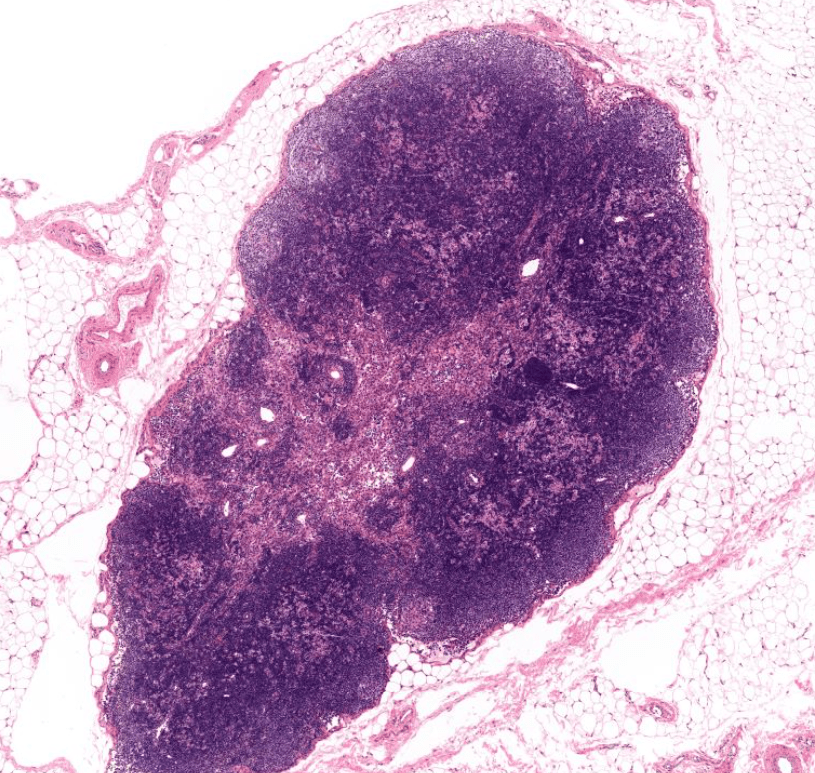

Observe el epitelio respiratorio que reviste las tonsilas faríngeas.Las amígdalas son acúmulos diferenciados de folículos linfoides situados debajo del epitelio de revestimiento de los puntos de entrada al tubo digestivo y al aparato respiratorio.Identifique el epitelio de revestimiento y las criptas palatinas.Las criptas palatinas son espacios en forma de «grietas» y son características de las amígdalas.El epitelio plano estratificado sin estrato córneo reviste las tonsilas palatinas,Amígdala palatina, HyE. Observe los nódulos linfoides secundarios.Recuerda que la amigdalitis es especialmente común en los niños y a menudo acompaña a una faringitis. Amígdala palatina, HyE.Las amígdalas son estructuras parcialmente encapsuladas que carecen de vasos linfáticos aferentes pero que están drenadas por vasos linfáticos eferentes. Amígdala palatina, HyE.Observe la enorme cantidad de nódulos linfáticos que tienen las amígdalas. Amígdala palatina, HyE.